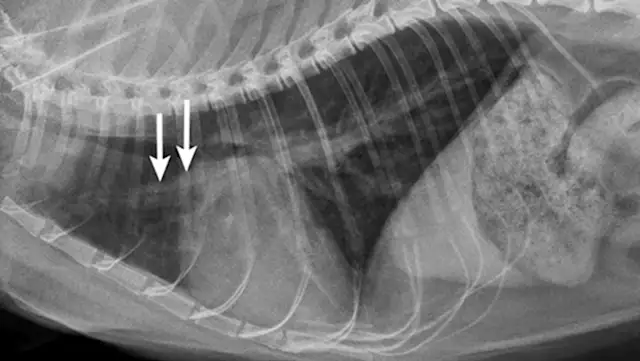

Primary cardiac disease that leads to CHF-related pulmonary edema commonly causes diffuse (perihilar in the dog) or variable (in the cat) interstitial and alveolar patterns. The vertebral heart score (VHS) is an objective method for evaluating the size of the cardiac silhouette (see Steps to Measure VHS). Certain cutoff values are used to determine whether acute respiratory distress is primarily pulmonary or cardiac in origin and to guide initial therapy for stabilization and planning for definitive cardiac or respiratory workup. A VHS <11.4 in the dog can help rule out mitral valve disease–related CHF as a cause for respiratory signs.3 Although an increased VHS can be associated with primary cardiac disease, it is not a specific characteristic in small-breed dogs because of their thoracic conformation.3 In the cat, a left lateral VHS ≤7.9 can reasonably rule out the presence of heart disease.4 Additional radiographic changes associated with primary cardiac disease include left atrial enlargement and pulmonary venous distension (Figures 1 and 2). Pleural effusion can be associated with CHF and primary pulmonary disease. A miliary pattern and/or solitary soft tissue densities in the lungs are indicative of primary pulmonary disease (Figure 3). Hyperinflation of the lung and distinct peribronchial markings are supportive of lower airway disease, although peribronchial markings can be found in the cat with CHF.

Mixed cardiac and pulmonary disease can exist in small animals with respiratory distress. For example, a dog may be presented with a history of mitral valve insufficiency but have clinical and radiographic evidence of aspiration pneumonia following a dental prophylaxis; or, a cat may present with a heart murmur and evidence of lower airway disease based on breathing pattern and thoracic radiographs (Figure 4; see image gallery above).